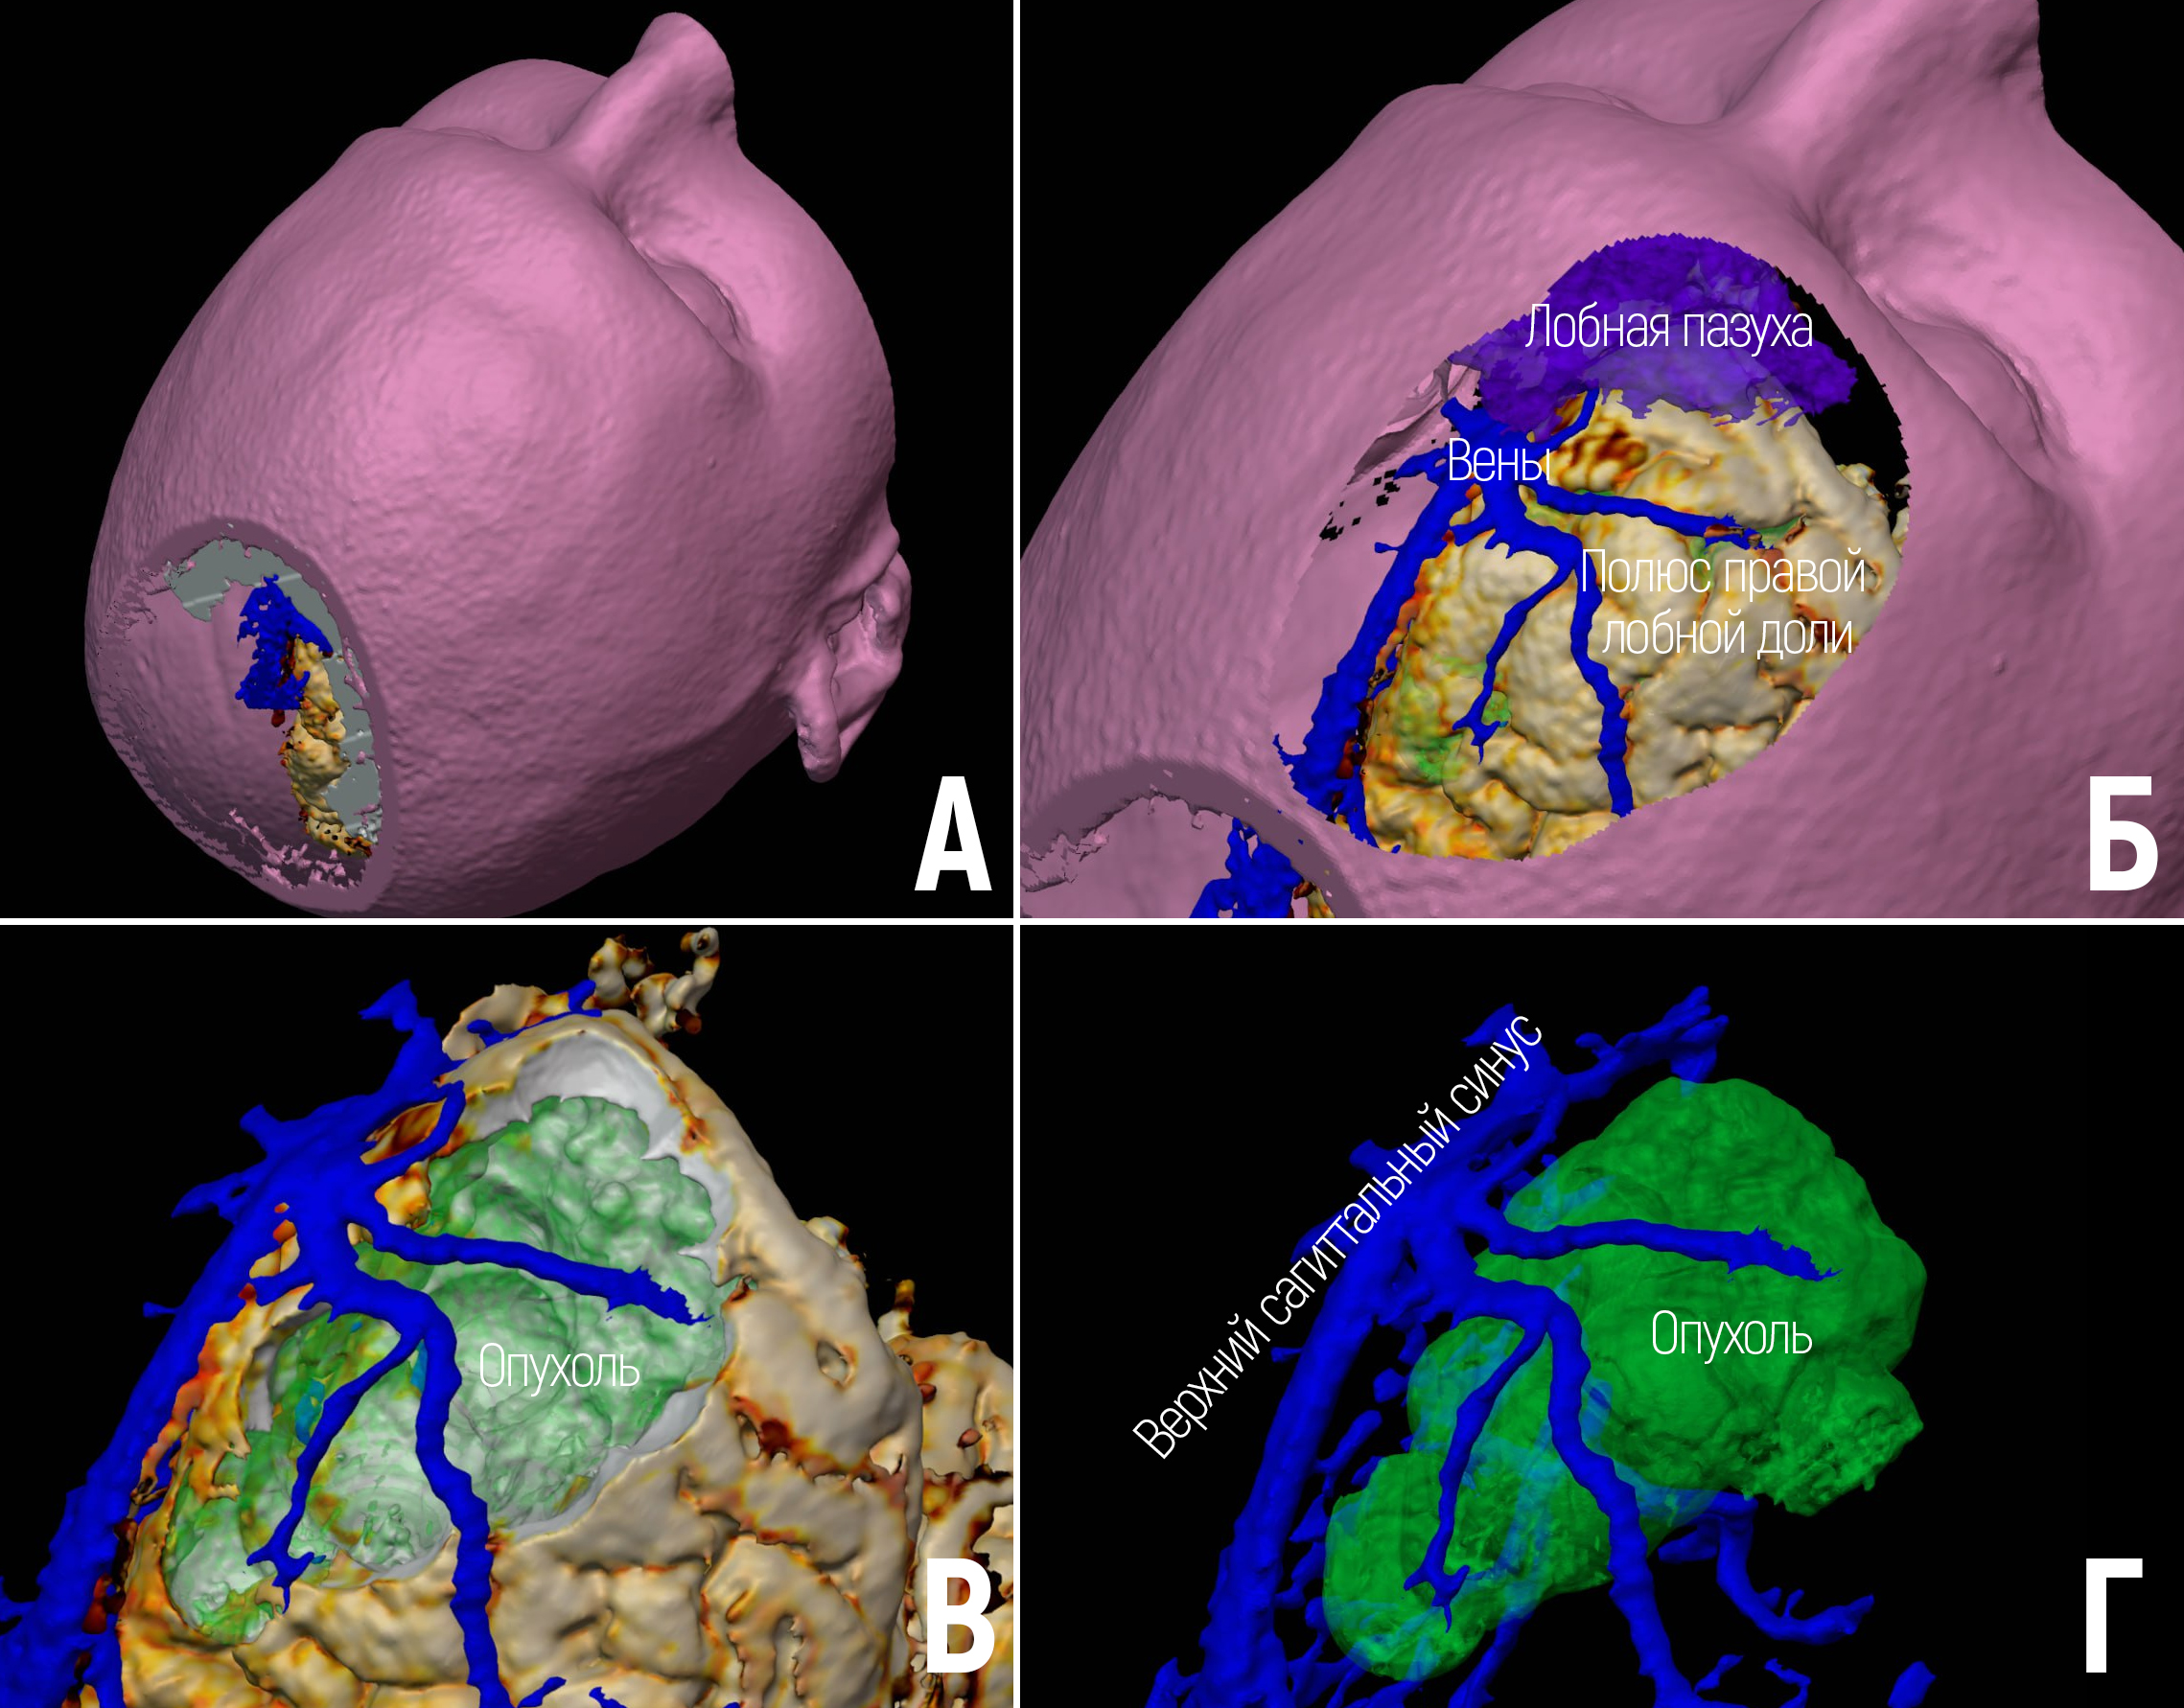

Цель – описание метода создания и опыта использования VR-библиотеки нейрохирургической интракраниальной патологии. Материалы и методы. Для создания 3D моделей использованы КТ и МРТ изображения. Сегментация производилась в программе Inobitec. Воспроизведение 3D моделей выполнялось в Blender с помощью VR-очков Oculus Quest 2. Результаты. Создана VR библиотека на основании данных 100 пациентов. Представлены 3 клинических наблюдения использования VR технологии. Заключение: VR-библиотека позволяет изучать индивидуальную анатомию пациентов, улучшать планирование операции.